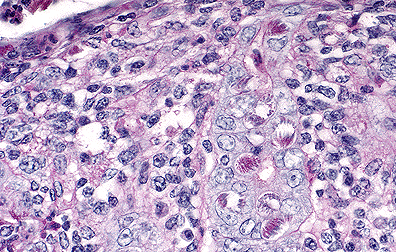

Iintraepithelial coccidial schizonts in the colonic epithelium of a calf. (100X, HE, 114K)

Microscopic lesions vary in appearance among the histological slides. In the section of colon examined, clumps of fibrin containing cellular debris and inflammatory cells are adhered to the mucosa. Most crypt epithelial cells contain schizonts, gamonts, or developing oocysts. Many intestinal crypts are distorted or have been destroyed as a result of coccidial infection. Erosion and ulceration of the mucosa have occurred. A lymphoplasmacytic inflammatory reaction is present in the lamina propria.

The most likely etiologic agent is Eimeria zuernii which is one of the most common and pathogenic coccidia of ruminants. The other is E. bovis. Life cycles of both agents are similar. Large schizonts typical of either E. bovis or E. zuernii were not observed in multiple sections of jejunum and ileum examined. Eimeria bovis infects endothelial cells in lacteals of the jejunum located several meters anterior to the ileocecal valve; whereas, E. zuernii schizonts are found in the lamina propria of the terminal ileum. Secondary schizonts and gamonts of E. zuernii develop in the glands of the cecum and colon but not terminal ileum.

AFIP Diagnosis: Colon: Colitis, necrotizing, subacute, diffuse, moderate, with erosions, and myriad intracellular coccidia, Hereford-cross, bovine, etiology consistent with Eimeria sp.